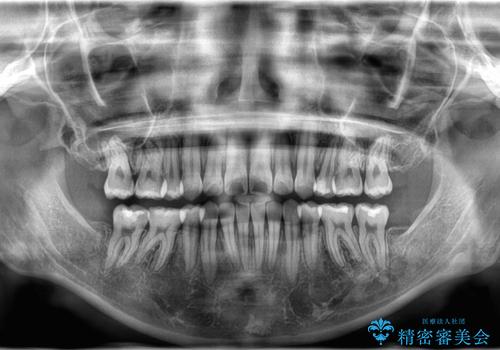

- 八重歯と口元が出ていることを主訴に来院されました。

レントゲンの検査において、前歯も外側に傾いてる結果であったため、上下左右の小臼歯を抜歯して配列を行いました。

歯の動きも良く短期間で治療を終えられたため患者さんにも大変満足していただきました。